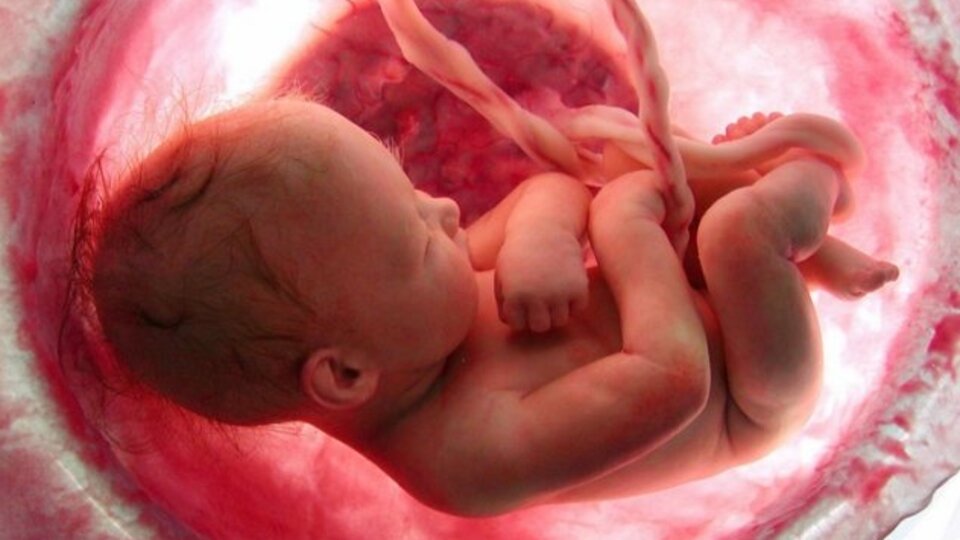

Çocuk beyin cerrahisindeki teknolojik gelişmelerin tanı koymaktan, tedaviye kadar birçok alanda yenilikleri de beraberinde getirdiğini anlatan Prof. Dr. Memet Özek, anne karnında yapılan omurilik ameliyatları ile ilgili çok önemli açıklamalar yaptı. Prof. Dr. Memet Özek; “Fetal cerrahi Türk Nöroşirürji Derneği’nin 30. Bilimsel Kongresi’nin de tartışma konularından birisiydi. Bebek anne rahmindeyken bir sorun saptanıyor ve bu sorunu çözmek için bebek anne rahminden dışarı çıkarılıp, ameliyat yapılıp tekrar yerine konuluyor. Gebeliğin 20. ve 26. haftalarında yapılan bu ameliyatlar bundan 15 yıl önce hayal olarak düşünülebiliyordu. Anne rahminde omurilik ameliyatları ülkemizde çok önemli bir sağlık sorunu olan spina bifida hastalığında yapılabiliyor” dedi.

Spina bifida hastalığı hakkında bilgiler veren Prof. Dr. Memet Özek; “Türkiye’de dünyaya gelen her 1000 bebekten 3 tanesi sipina bifida ile yani bebeğin anne rahminde omuriliğinin iyi gelişememesi, açık kalması ile doğuyor. Bunun sonucunda bebeğin ayak hareketlerinde yürüyememeye kadar varan sorun, idrar, dışkılama problemleri, ilerleyen yaşlarda cinsel fonksiyonlarda bozukluklar gibi insan hayatını, sosyal hayatı etkileyen hayli ciddi sorunlarla karşılaşması demek anlamına geliyor” dedi. Spina bifida hastalığını daha bebek doğmadan anne rahminde tedavi etmek için önemli ameliyatların başladığını ifade eden Prof. Dr. Memet Özek; “şu andadünyada çok sınırlı sayıda deneme aşamasında yapılıyor. Ama iyi kontrolle, iyi teknik ve yetişmiş eleman katılımıyla gelecekte ülkemizde de anne rahminde spina bifida ameliyatları uygulanabilecek” şeklinde konuştu.

Anne rahminde omurilik ameliyatlarının ne gibi avantajlar sağlayacağından da bahseden Prof. Dr. Memet Özek; “Spina Bifida (Açık Omurga) hastalığı çocuklarda; motor ve omurilik problemleri, kısmi felçler, hidrosefali (beyinde sıvı toplanması) idrar ve büyük tuvaletini kaçırma, ileri böbrek yetmezliği ile skolyoz gibi bir takım hastalıklara neden oluyor. Her yıl 1 milyon 200 bin doğumun gerçekleştiği Türkiye’de, Spina Bifida görülme sıklığı binde üç olarak kaydediliyor. Bugüne kadar, bu hastalıkla dünyaya gelen bebekler hemen akabinde ameliyata alınırken, neredeyse tamamında kalıcı hasarlar meydana geliyordu. Birçok ailenin yaşamını altüst eden “Açık Omurga” hastalığına karşı anne karnındaki bebeklere Spina Bifida ameliyatları dünyada bazı merkezlerde yapılmaya başlandı. Bu çocuklarda aynı zamanda hidrosefali (beyinde sıvı toplanması) dediğimiz problem oluyor. Amerika’da yapılan çalışmalar bu sorunun önlenebileceğini, yürümeyle ilgili bazı avantajlar sağlanabileceğini gösteriyor” dedi.